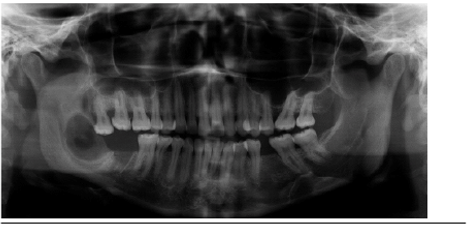

En julio de 2014 se presenta en el Servicio de Cirugía Maxilofacial del Hospital Clínico San Borja Arriarán una paciente de sexo femenino, 46 años, con un aumento de volumen mandibular derecho comunicado a boca a través de una perforación de la mucosa generada hace tres años al momento de la extracción del tercer molar (Figura 1 y 2). Al examen imagenológico (Radiografía y Tomografía) presenta una gran zona radiolúcida que compromete cuerpo y rama mandibular (Figura 3).

La biopsia reveló ameloblastoma sólido mandibular, un tumor odontogénico benigno ubicado en la mayoría de los casos en la mandíbula8. El tratamiento corresponde a la resección de los segmentos óseos comprometidos con margen de seguridad, dada su alta tasa de recidiva9,10.